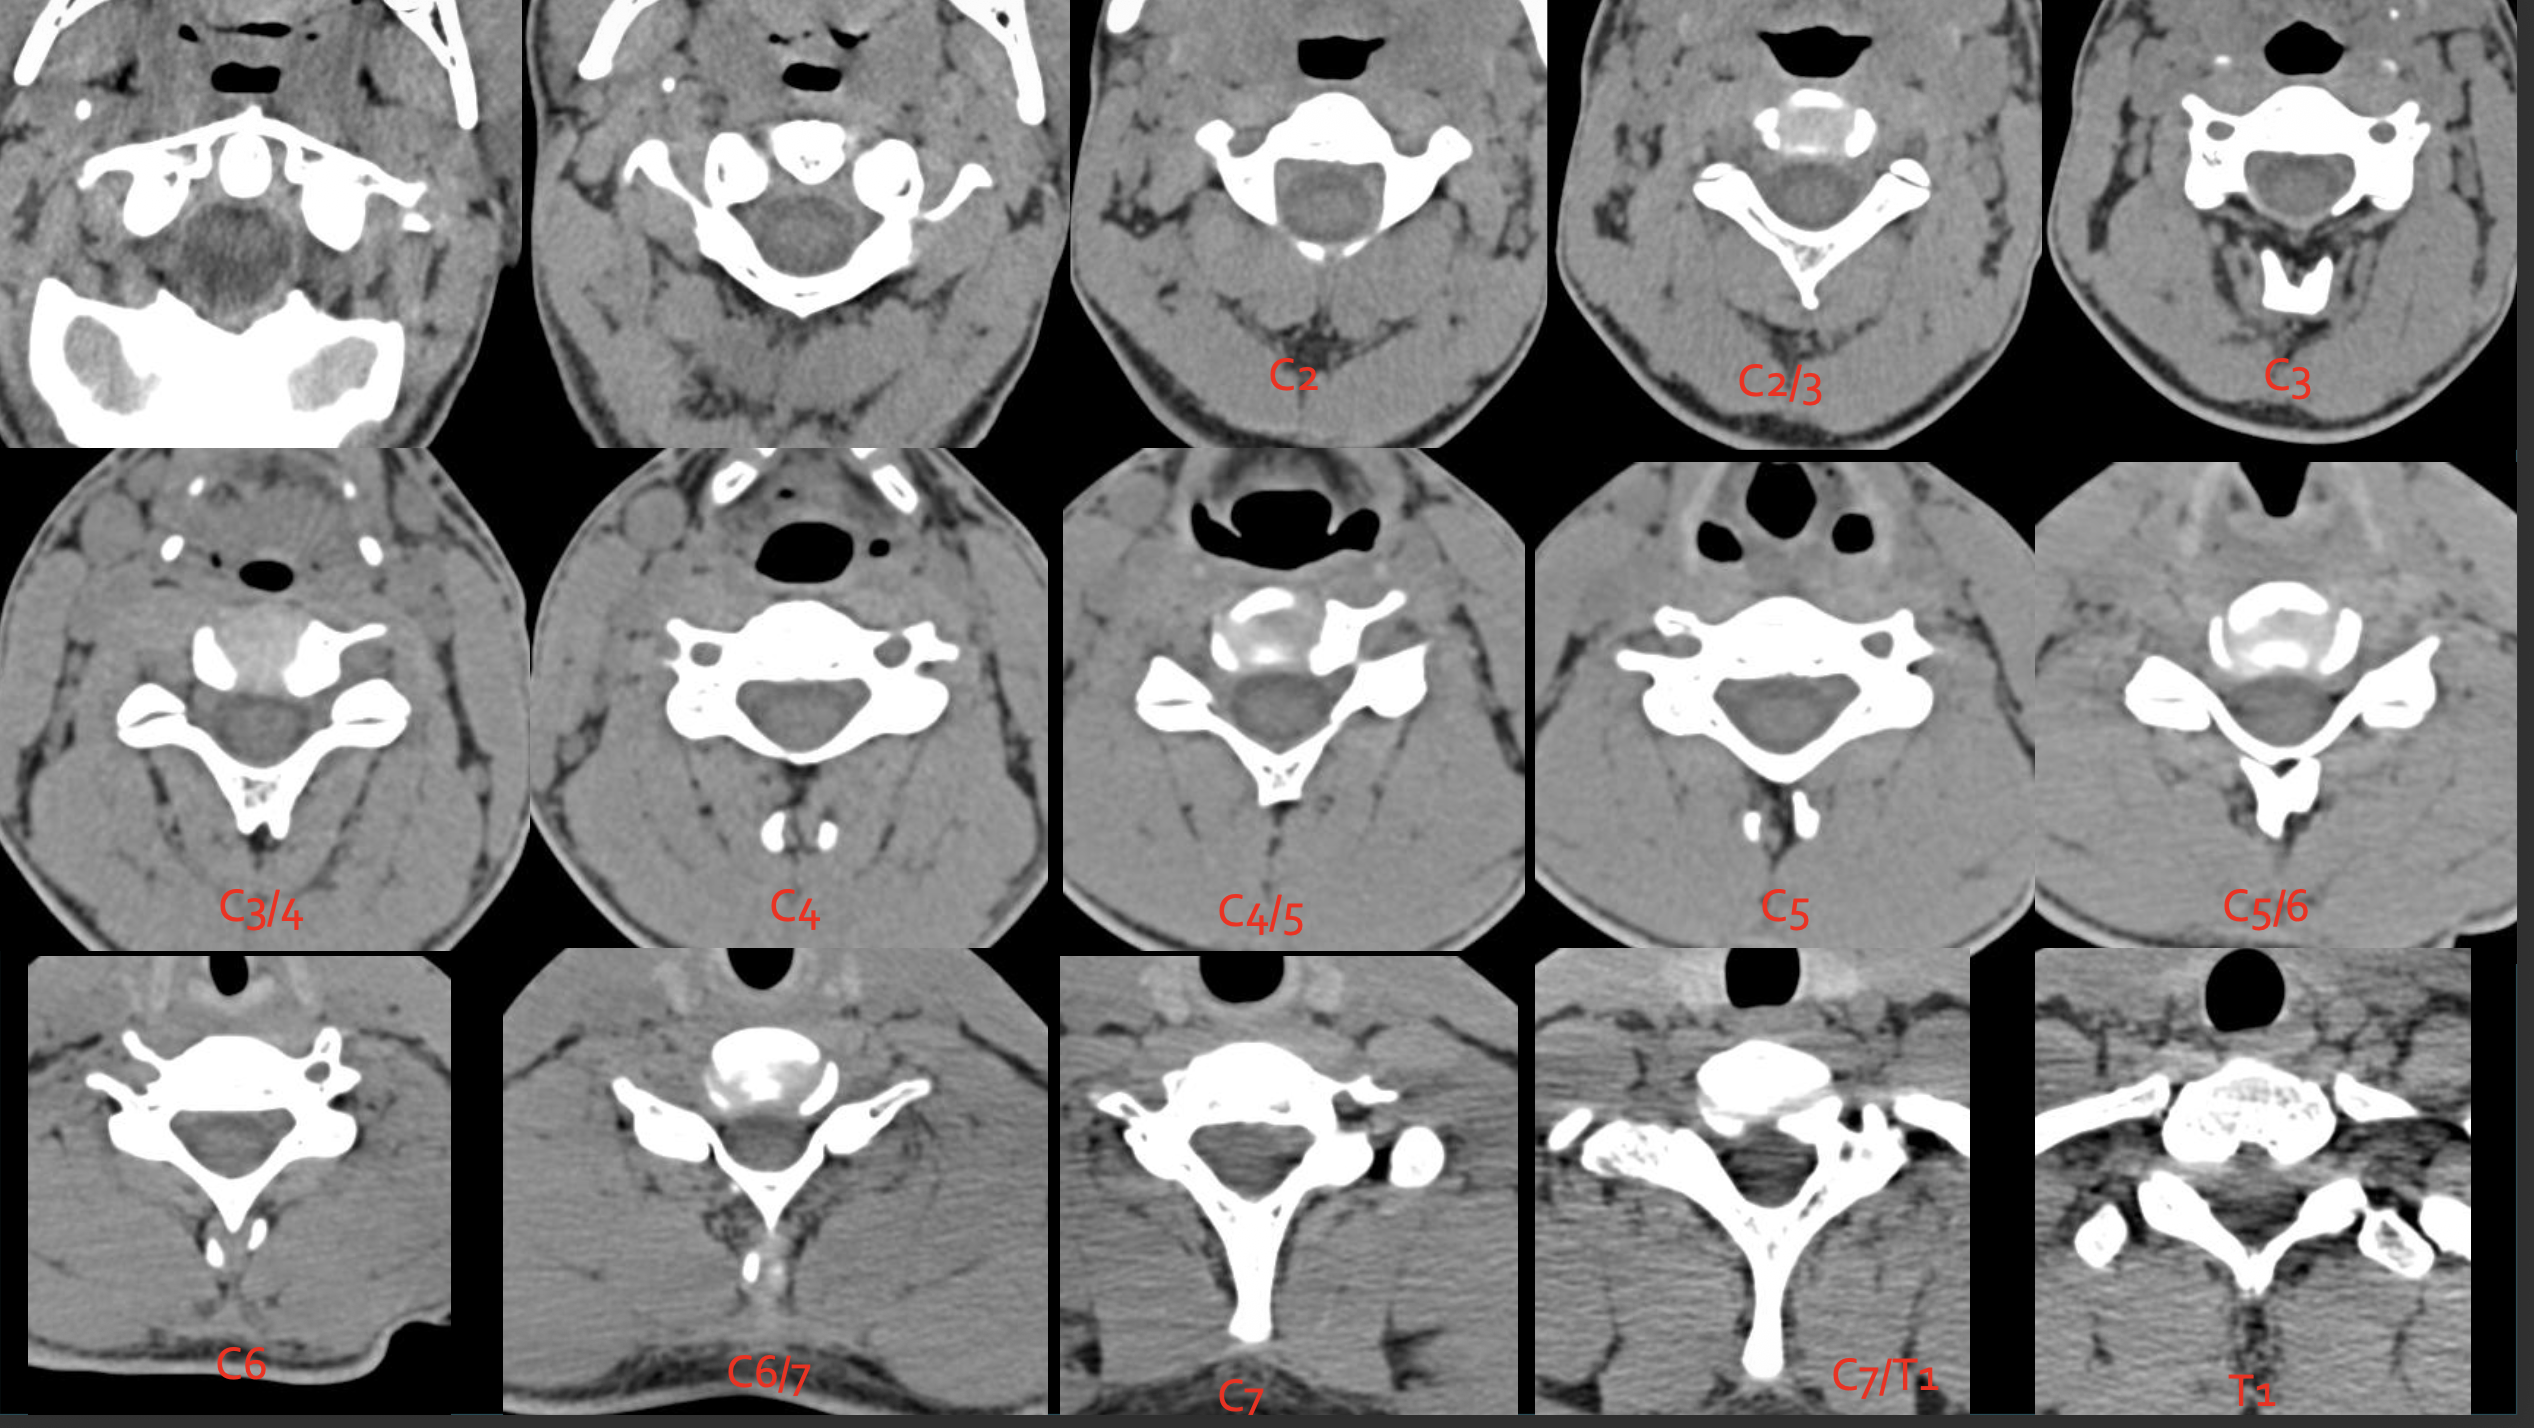

C2

C3

C4

c5

c6

c7

T1

C1